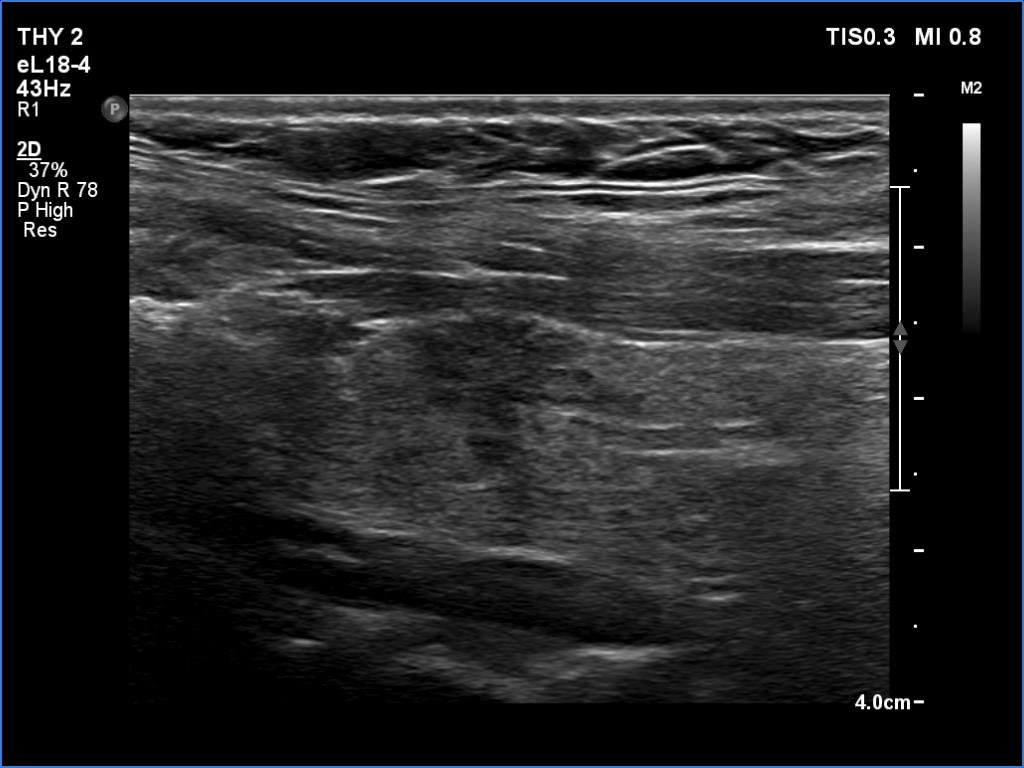

Second examination 2 years later (third rows of images):

Both the ultrasound and the cytological patterns remained unchanged.

Comments. The discrete lesion in the left lobe is highly suspicious, and even after two reassuring cytological findings, some suspicions remain. Two considerations. Firstly, the largest diameter of the lesion was 10 and 9 mm, first and second examination, respectively. All TIRADS are contradictory on the indication of cytology: according to their main tables, cytology is not justified, while all argue in the text that cytology may be considered in the case of a nodule with a suspicious sign no larger than 1 cm. Secondly, ultrasound follow-up is clearly advisable in such cases.